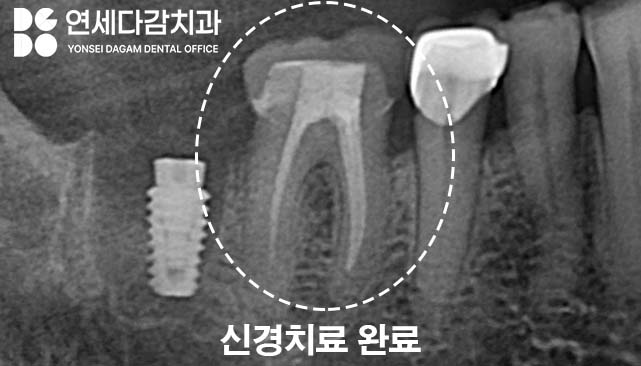

가락시장역 치과 에서는 이런 경우 크라운을

제거하고 내부 상태를 확인합니다.

예상대로 치아에 금이 발견되면

신경치료를 시행합니다.

신경치료 후에는 상태를 지켜보는 것이

좋습니다.

균열의 깊이와 범위에 따라 예후가

달라지기 때문입니다.